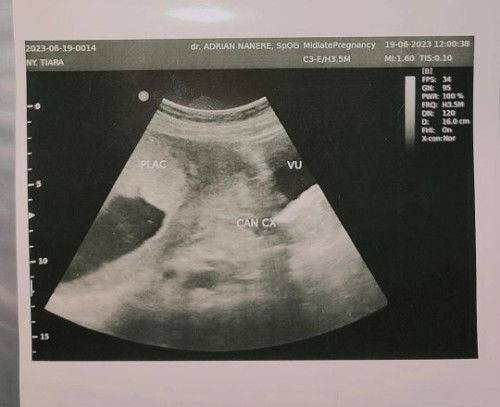

PLAC: Placenta CAN CX: Jalur Lahir Halo bun, usia kandunganku 25week, kemarin cek usg posisi plasentaku kurang baik, posisinya sedikit agak dibawah hampir menutupi jalur lahir. memang kata dokternya ini masih bisa berubah keatas dalam 1 bulan kedepan, kalau sudah di usia 28-29week katanya tidak bisa berubah. nah kalau plasentaku tidak berubah di usia 28-29 week, maka aku harus melahirkan secara SC. aku ga masalah sama SC, cuma sebisa mungkin aku ingin lahiran normal. ada tipsnya ga ya bun supaya plasenta naik keatas, kemarin lupa nanya ke dokter saking shocknya karna overthinking, mohon bantu jawab ya bun, soalnya ini anak pertama, dan aku masih belum tau banyak tentang kehamilan. #seriusnanya #bantusharing #ingintahu #firstmom #pleasehelp #firstbaby